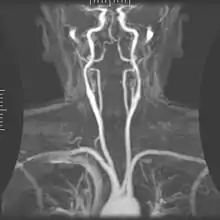

Magnetic resonance angiography (MRA) generates pictures of the arteries to evaluate them for stenosis (abnormal narrowing) or aneurysms (vessel wall dilatations, at risk of rupture). MRA is often used to evaluate the arteries of the neck and brain, the thoracic and abdominal aorta, the renal arteries, and the legs (called a "run-off"). A variety of techniques can be used to generate the pictures, such as administration of a paramagnetic contrast agent (gadolinium) or using a technique known as "flow-related enhancement" (e.g., 2D and 3D time-of-flight sequences), where most of the signal on an image is due to blood that recently moved into that plane (see also FLASH MRI).[51]

Techniques involving phase accumulation (known as phase contrast angiography) can also be used to generate flow velocity maps easily and accurately. Magnetic resonance venography (MRV) is a similar procedure that is used to image veins. In this method, the tissue is now excited inferiorly, while the signal is gathered in the plane immediately superior to the excitation plane—thus imaging the venous blood that recently moved from the excited plane.[52]